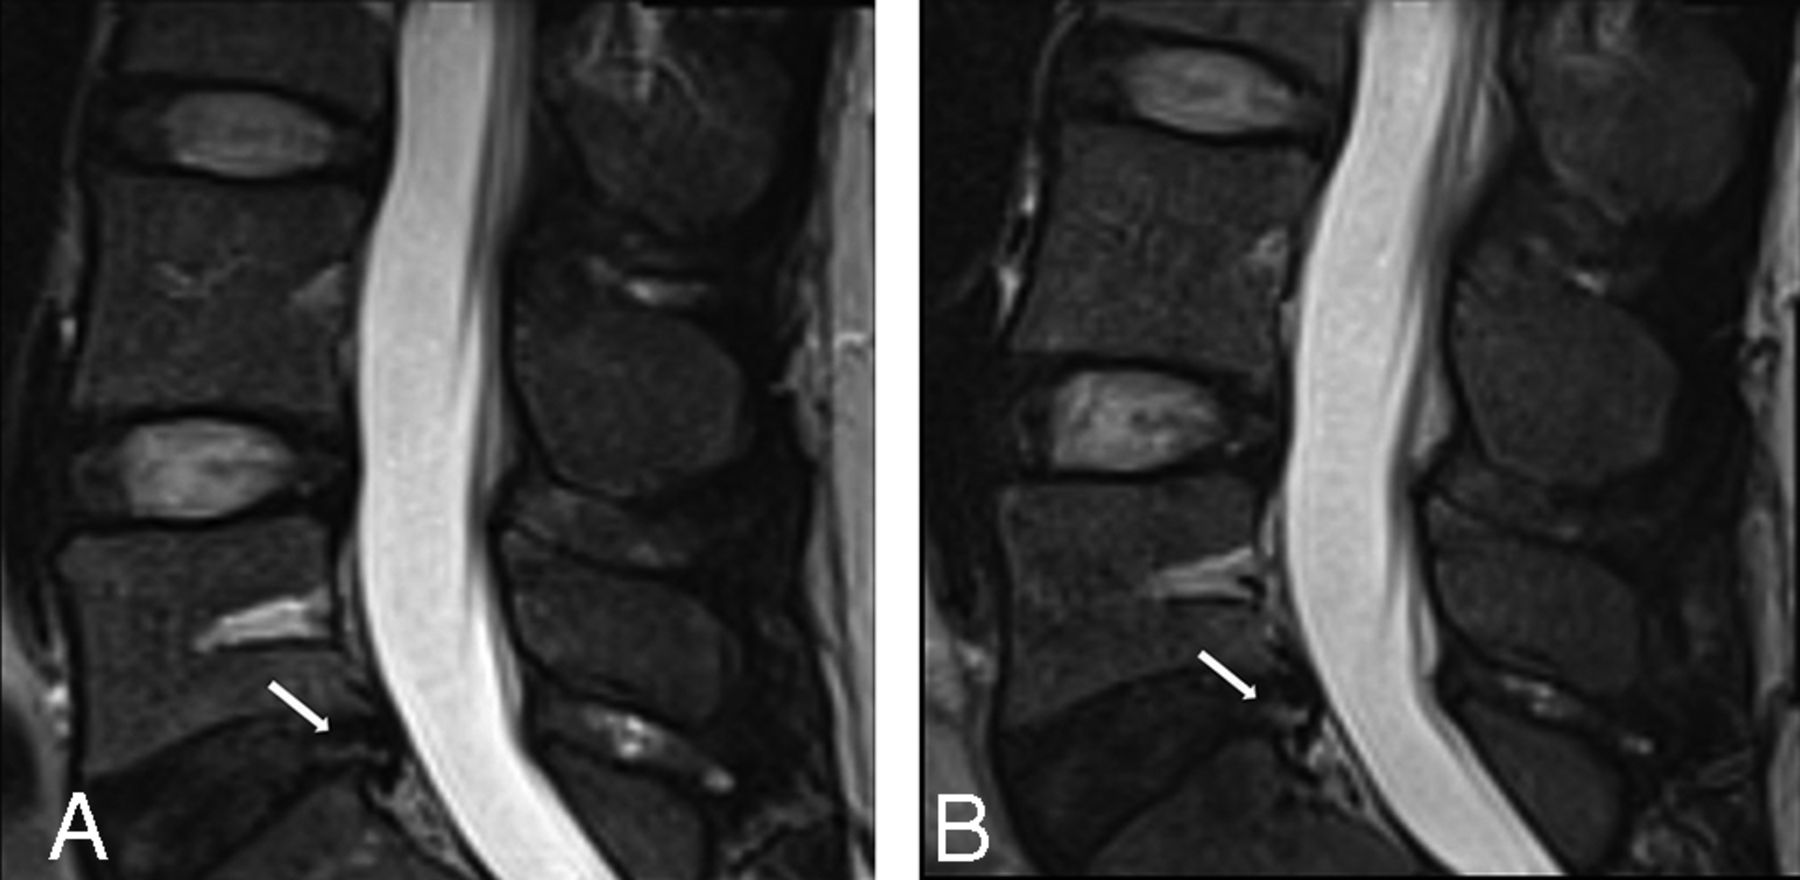

Images of an annular fissure from 1 participant with LBP showing an example of definite change.